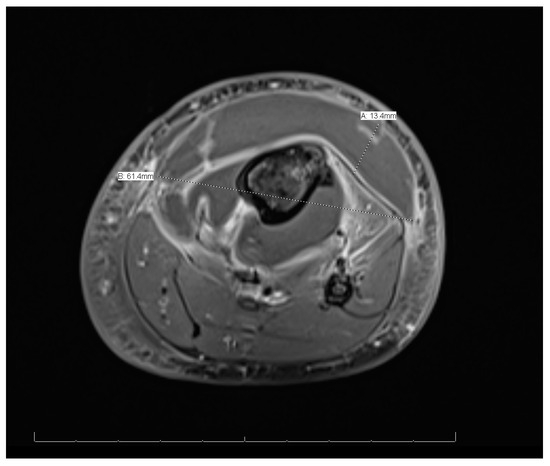

MRI of the left leg (Figure 3 and Figure 4): The whole left tibial bone shaft (proximal, mid, and distal), including the proximal epiphysis, showed a diffuse, multiple, heterogeneous marrow signal, intermediate to low on T1 and high on T2, as well as bone marrow edema associated with a periosteal reaction seen mainly on the medial aspect of the proximal metaphysis of the tibia. This is a large lobulated/septated periosteal collection surrounding all aspects of the proximal region and the mid-shaft of the left tibia bone. The collection ran along posteriorly for a distance of 13.3 cm × 3.2 cm × 1.4 cm (cranio-caudal [CC], medial–lateral [ML], and anterior–posterior [AP], respectively), with a small pocket extending to the posterior muscle compartment involving the knee joint, which showed joint effusion and synovitis. The anterior part of the collection extended partially to the anterior subcutaneous area and measured 13 × 5.7 × 1.6 (CC, ML, and AP, respectively). Both the anterior and posterior parts of the collections were connected. A focal cortical defect was evident at the anterior medial aspect of the proximal tibial epiphysis (T2 STIR axial 15/44 image), with an adjacent periosteal collection. The fibula, femur, and ankle joint were not involved and showed a normal signal. Diffuse soft tissue swelling was evident, mainly in the proximal part of the leg. The muscles around the leg and knee joint appeared to be normal. The MRI findings were in line with acute osteomyelitis of the left tibia, with periosteal collections.

Figure 4.

Magnetic resonance imaging of the whole left leg (cross-sectional view).

This case showed distant metastatic emboli to the left leg. Other studies showed different sites, such as the lungs [10]. Similarly to other cases, this case was treated without surgical interventions because there was no obvious surgical necrosis that necessitated debridement, and cases requiring surgical interventions are rare [10]. The sign that indicated migration was that swelling of the left leg began after the fever onsite. In addition, the imaging modalities for this patient, including MRI, indicated migration.